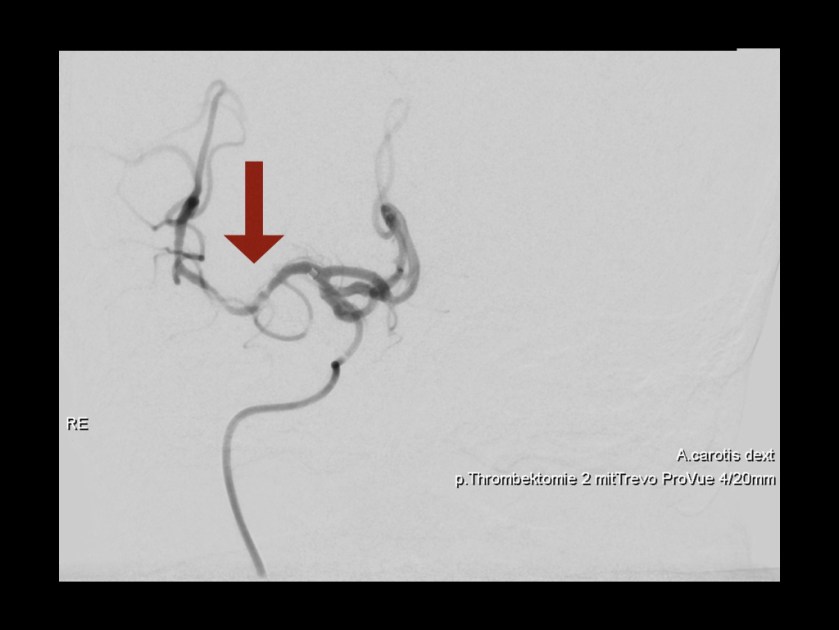

DSA – Rekanalisierung:

Erfolgreiche Rekanalisierung (Pfeil) und somit Reperfusion um 10:59 Uhr.